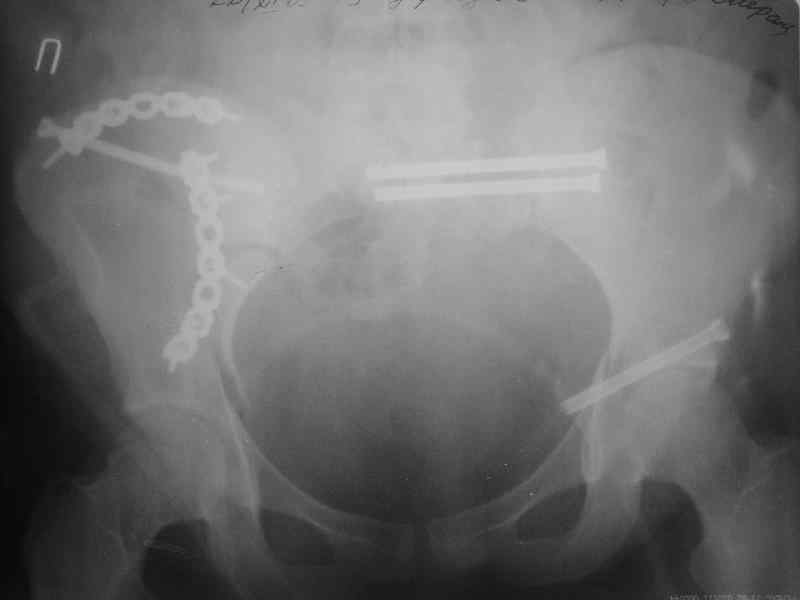

Здравствуйте, коллеги. Какие будут мнения по поводу лечения представляемой больной?

Молодая девушка 19 лет, травма 1 год назад, тогда же прооперирована.

В настоящее время имеются ноющие боли в области крестца слева, нарушение походки, ощущение неуверенности, слабости в левой нижней конечности, неврологически -непостоянные парестезии в левой нижней конечности. Ходит с дополнительной опорой, страдает от ожирения.

В приложении снимки при поступлении и послеоперационные год назад.

Могу сказать одно: миграция винтов и нестабильность синтеза левого подвздошно-крестцовогоо сочленения очевидна.